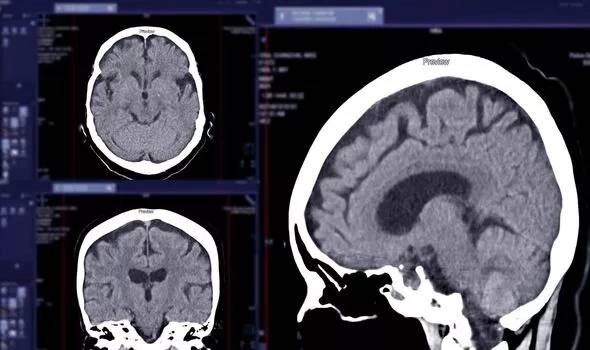

Sa sút trí tuệ xảy ra khi các protein độc hại tích tụ trong não và ngăn chặn sự giao tiếp giữa các tế bào não. Các dấu hiệu rõ ràng của bệnh thường là khó tập trung và mất trí nhớ, nhưng bệnh nhân đôi khi cũng có những triệu chứng khác, chẳng hạn như sự thay đổi trong giọng nói. Đôi khi, sự trôi chảy trong lời nói là một trong những manh mối đầu tiên gợi ý về sự suy giảm chức năng của não.